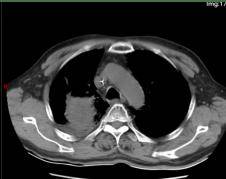

靶向治疗前

所谓的精准武器,就是当时国内新获批的可医保报销的高选择性MET抑制剂。1月12日,69岁的老李开始口服这种靶向药物——MET抑制剂。仅仅28天,咳嗽、痰血和喘憋就明显减轻。复查CT,原本被肿瘤压瘪的右上肺重新张开,连支气管镜下的“菜花”样新生物也缩小了近一半。老李高兴地说:“睡觉不再被憋醒,走路也能跟上儿子了。”